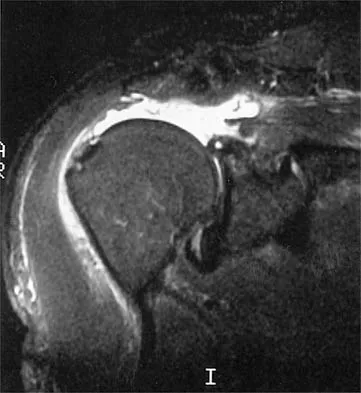

Question 70 High Yield

A 65-year-old woman sustained an axial load on the arm followed by an abduction injury after falling on ice. Treatment in the emergency department consisted of reduction of an anterior dislocation. She now has a positive drop arm sign and a positive lift-off test. An MRI scan is shown in Figure 9. Based on these findings, management should consist of

Detailed Explanation